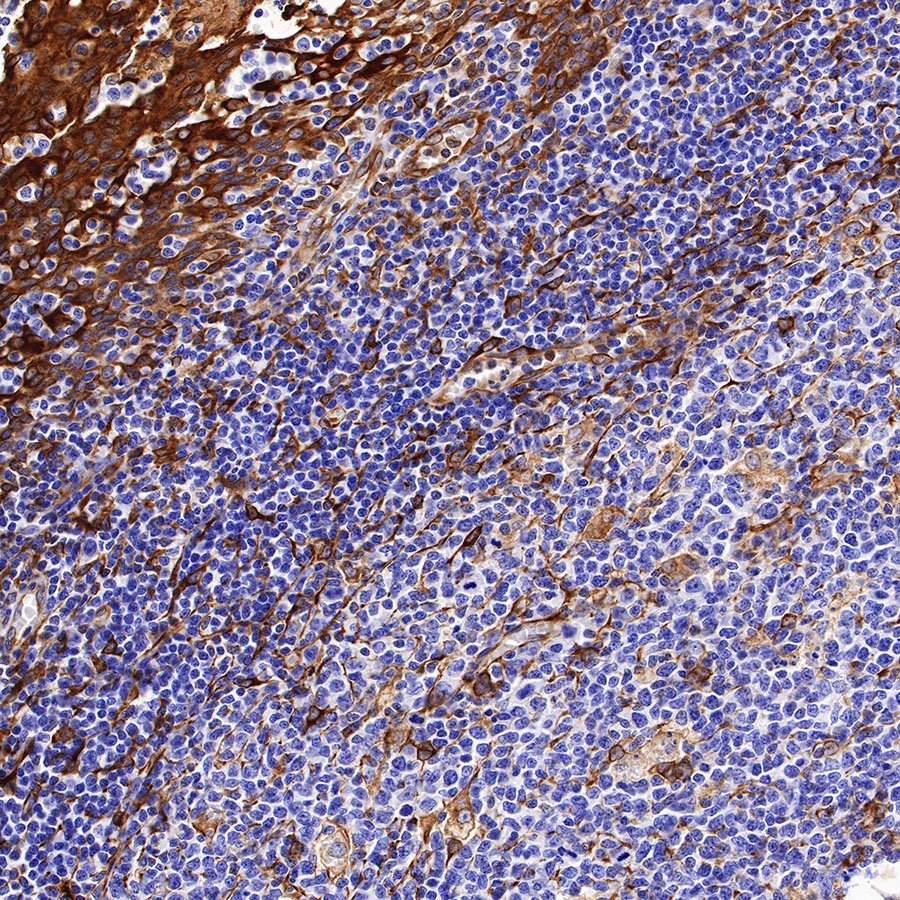

Picture

Picture

Immunohistochemistry